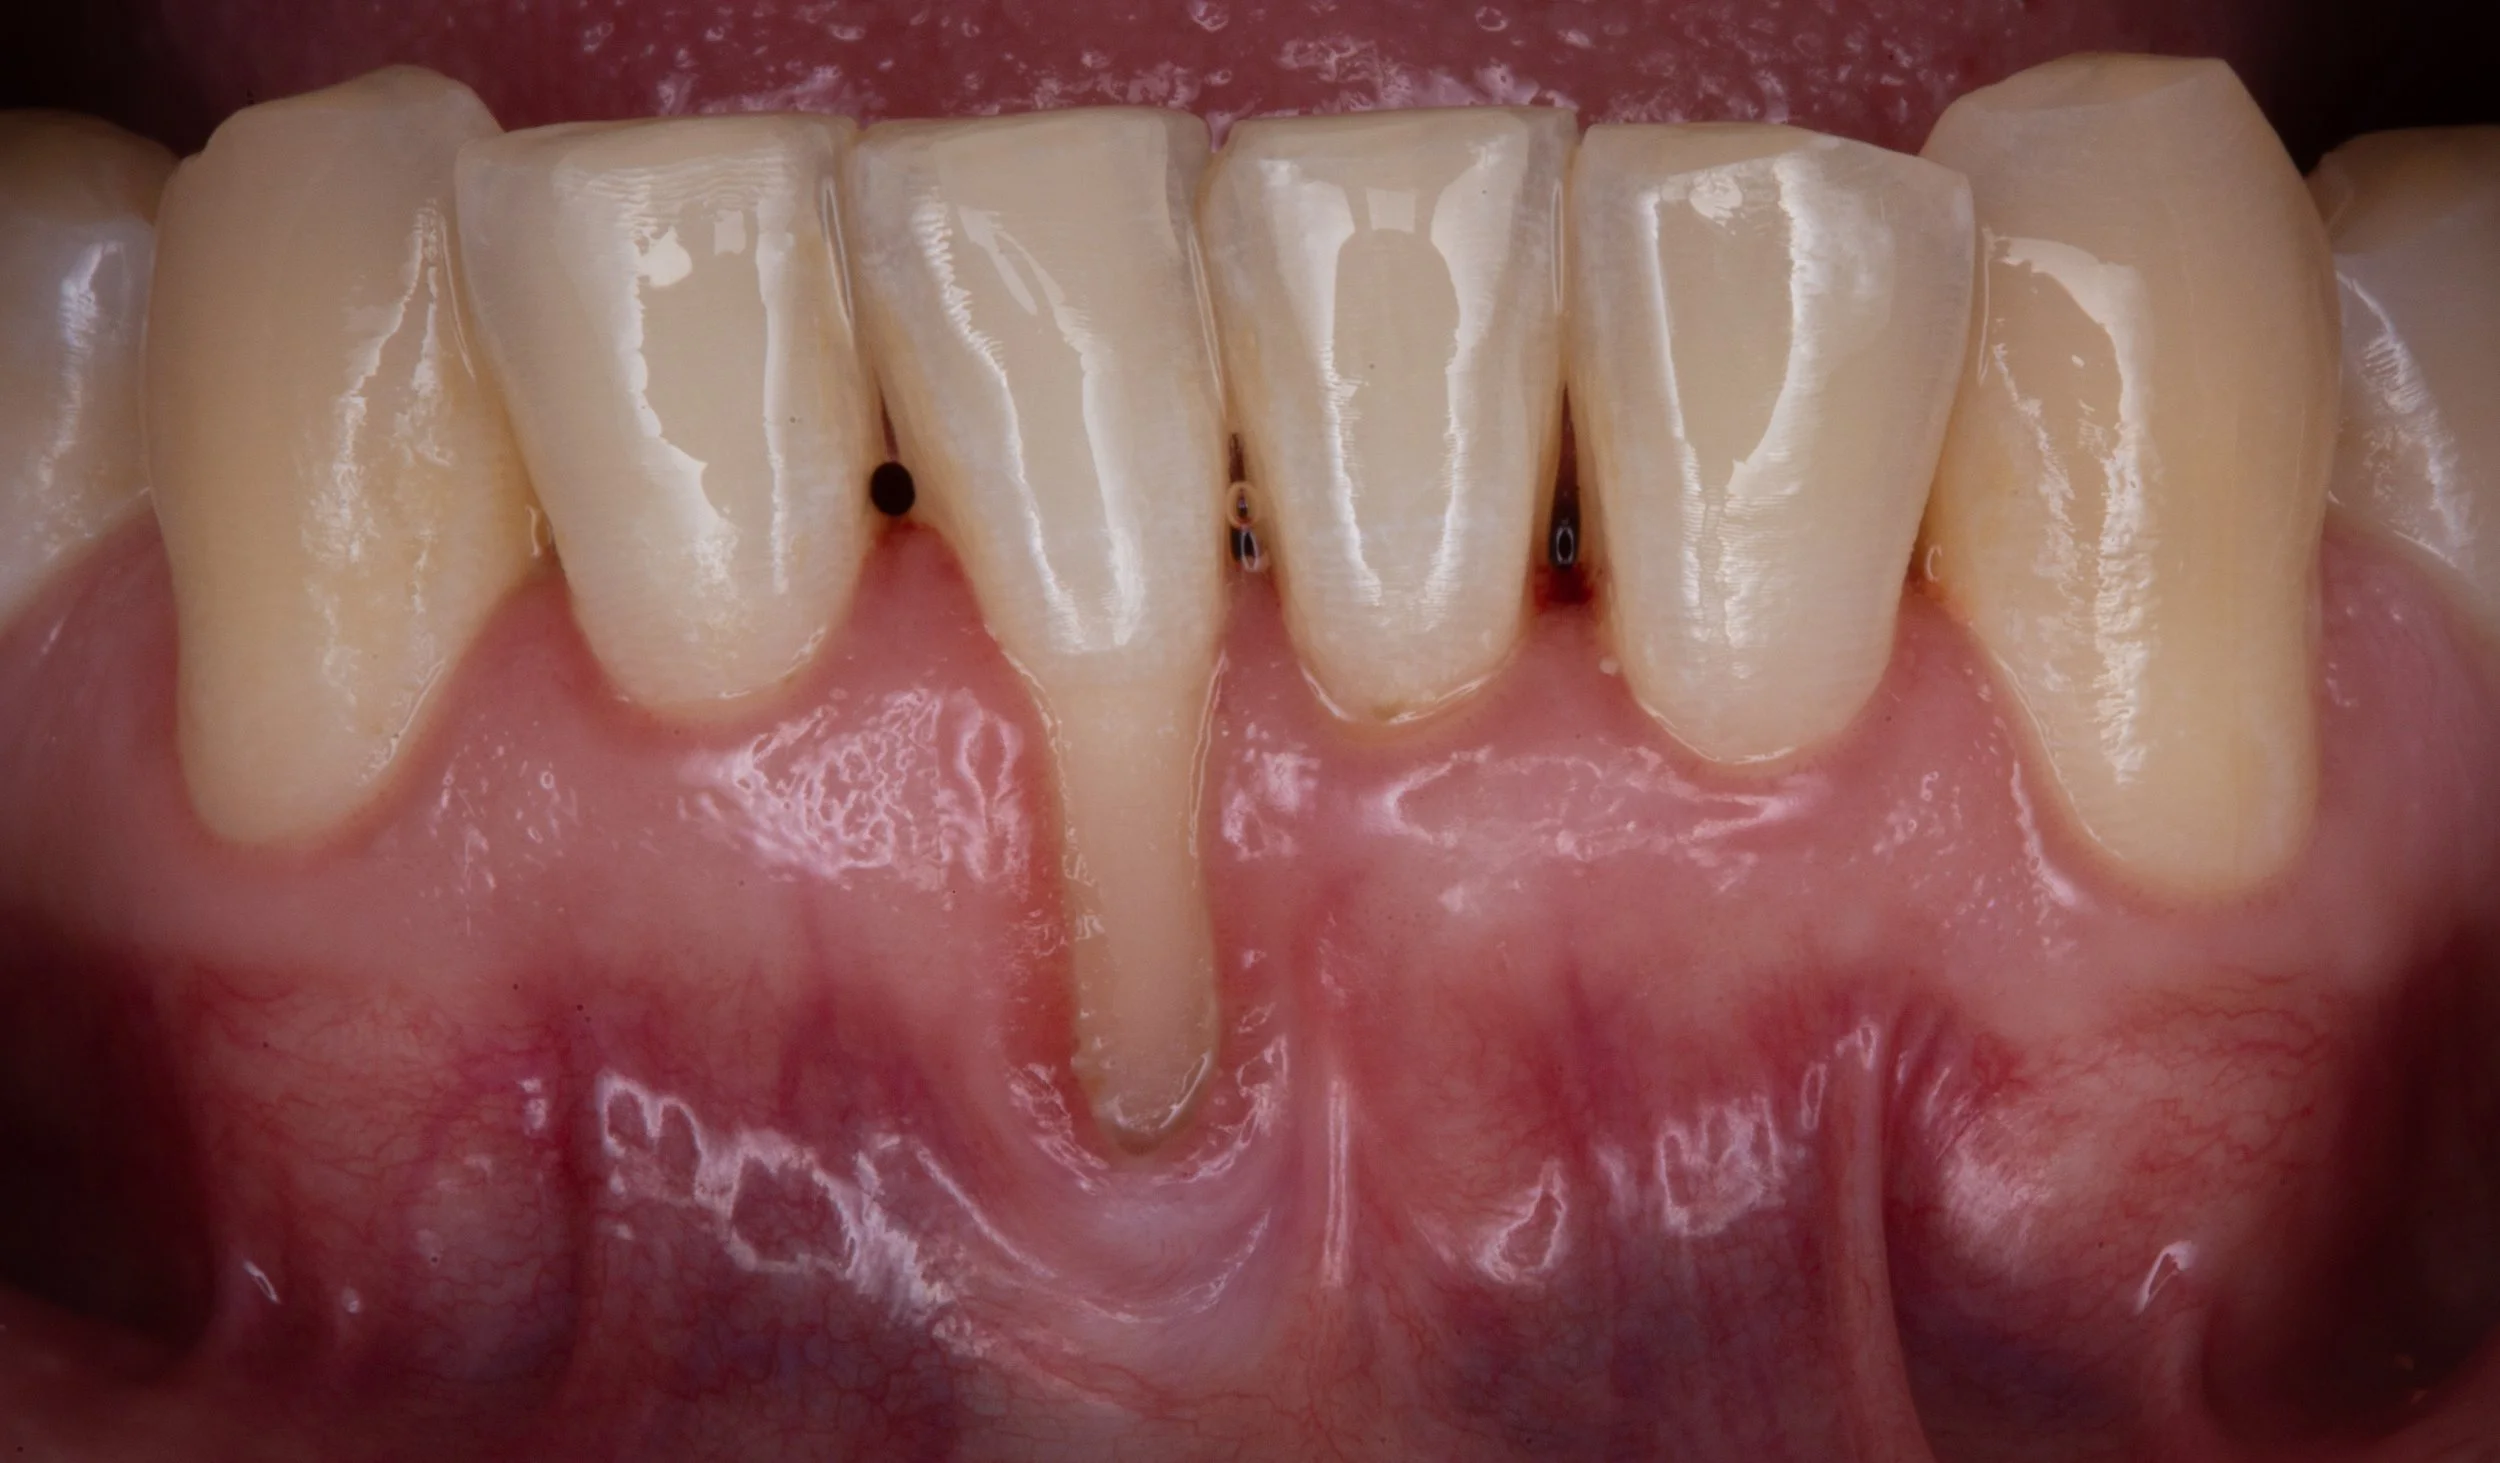

Sensitivity to cold, or bleeding after brushing your teeth may indicate gum recession. This occurs when your gums pull away from your tooth, exposing the root surface which may be uncomfortable or unsightly.